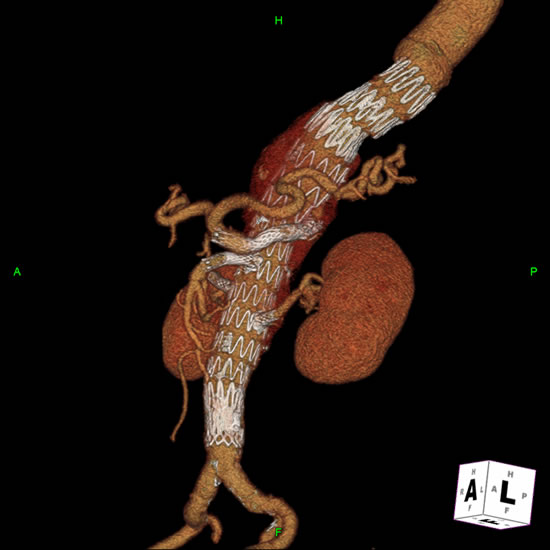

Follow-Up

The perioperative complications of TAAA repair have not been eliminated but their incidence is reduced and include renal dysfunction, respiratory failure, stroke, MI, and spinal cord injury [2]. Other late complications include endoleaks and therefore all patients need regularly scheduled follow-up CT imaging at months 1, 6, 12 and annually (Figure 5).